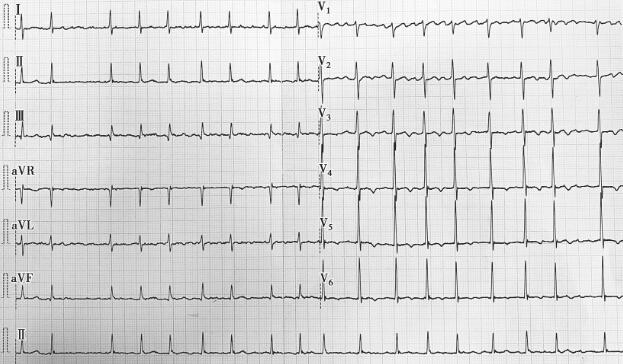

血常规、尿常规、粪便常规、肝肾功能、血脂、尿白蛋白/肌酐、凝血功能及甲状腺功能未见异常。心电图示(图1):心房颤动(简称房颤)。

图1 心悸发作时心电图